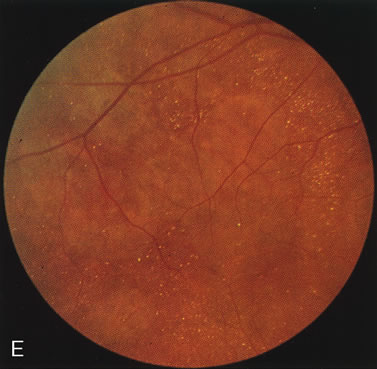

CONE DYSTROPHIES

Fluorescein angiography highlights observable fundus findings. In patients with a golden reflex the FA is normal (Fig. 2E, F) or shows a mild transmission hyperfluorescence.7